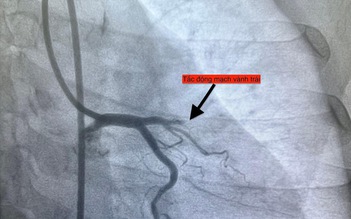

Nhồi máu cơ tim: Nhận biết, dự phòng và điều trị hiệu quả

Nếu không được phát hiện sớm và kiểm soát kịp thời, các yếu tố nguy cơ như: tăng huyết áp, rối loạn mỡ máu, xơ vữa động mạch… có thể dẫn đến biến cố nghiêm trọng như nhồi máu cơ tim.